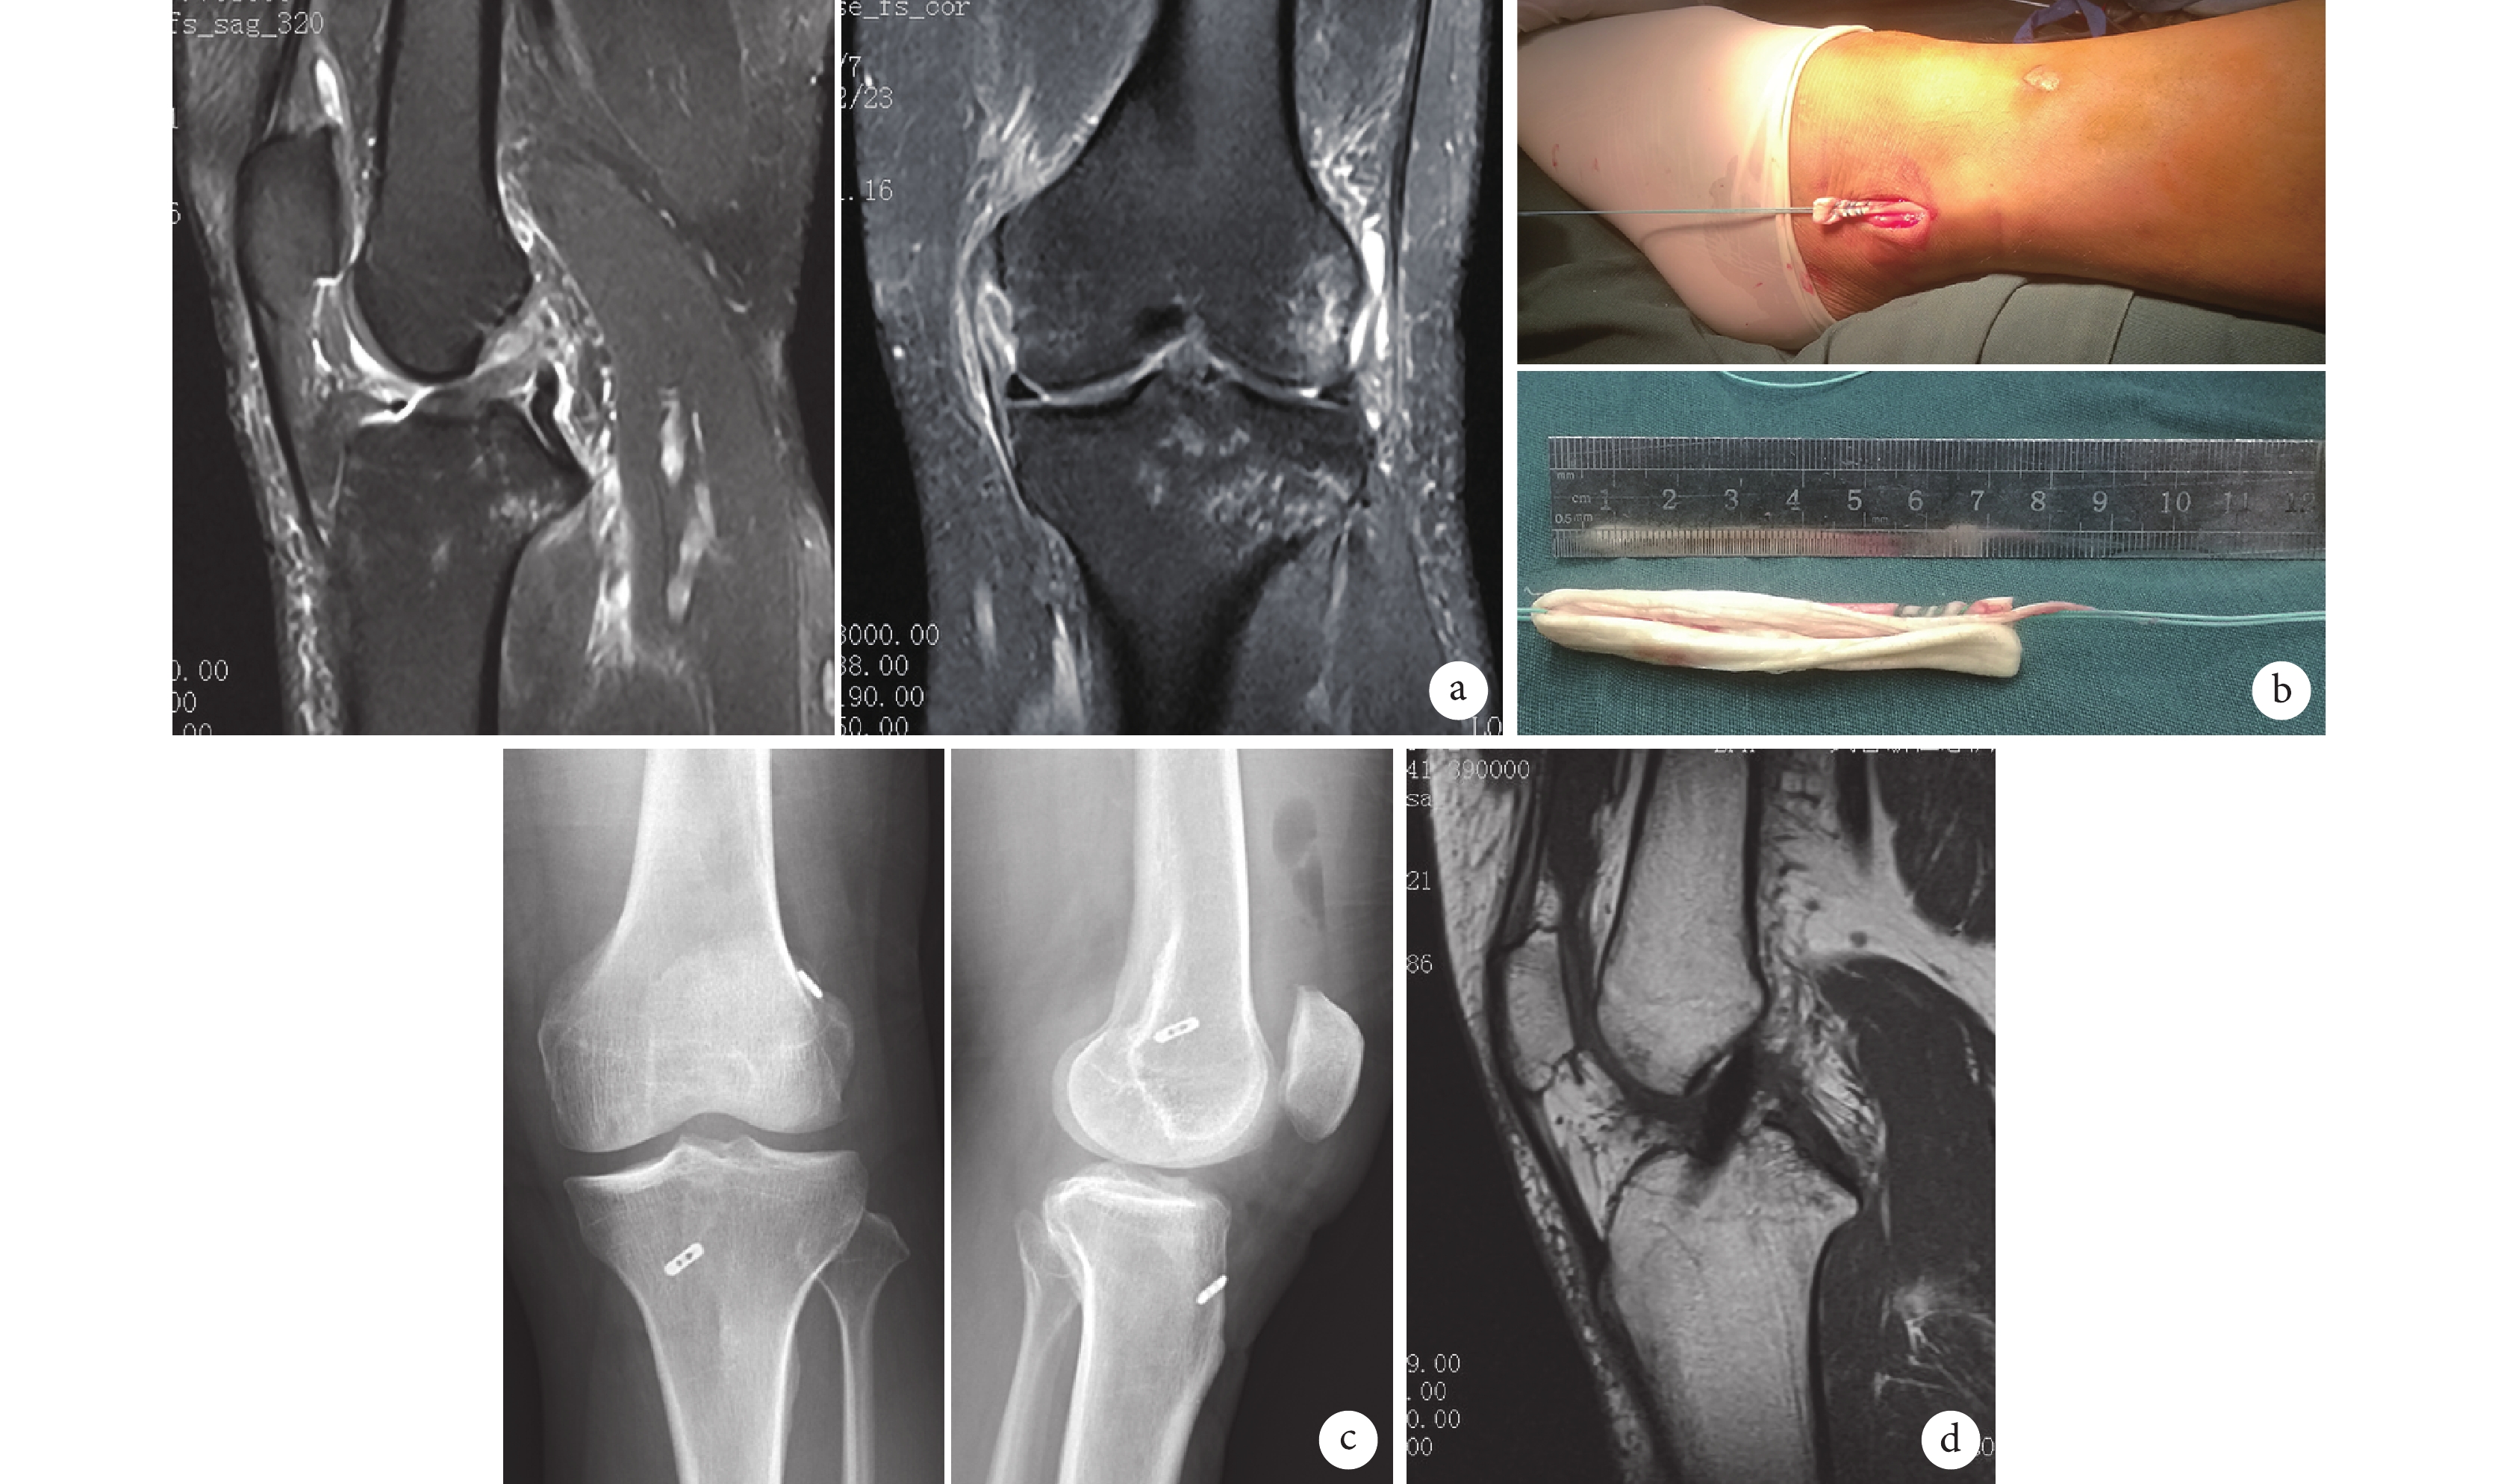

本組手術時間 55~90 min,平均 72.5 min。術后切口均Ⅰ期愈合,無手術相關并發癥發生。患者均獲隨訪,隨訪時間 6~38 個月,平均 20.7 個月。術后患者均對膝關節穩定性滿意,運動能力基本恢復。術后 3 個月膝關節活動度為 116~132°,平均 122°。Lachman 試驗 2 例脛骨前移<5 mm,其余均為陰性;外翻應力試驗均為陰性。術后 6 個月膝關節 Lysholm 評分為(90.2±1.8)分,IKDC 評分為(93.5±2.3)分,明顯高于術前,差異有統計學意義(t=31.60,P=0.00;t=29.91,P=0.01)。踝關節 AOFAS 評分為(97.86±0.68)分,與術前比較差異無統計學意義(t=2.89,P=0.08)。術后 6 個月,KT-1000 測量雙側膝關節前向松弛度差值<2 mm 者 25 例,3~5 mm 者 3 例。見圖 1。

a.術前 MRI;b.術中制備肌腱束;c. 術后 1 周膝關節正側位 X 線片;d. 術后 12 個月 MRI

Figure1. A 44-year-old female patient with the left ACL rupture and MCL grade Ⅲ injurya. Preoperative MRI; b. Intraoperative preparation of tendon bundles; c. Anteroposterior and lateral X-ray films of knee joint at 1 week after operation; d. MRI at 12 months after operation